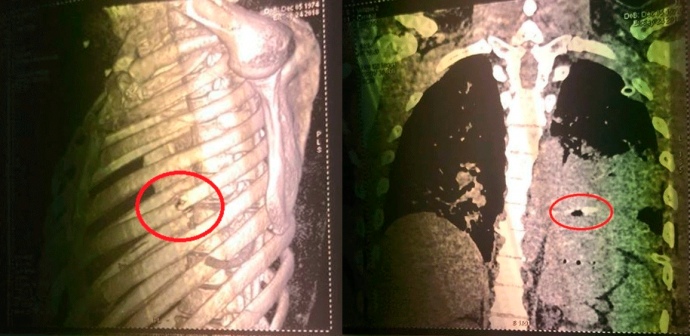

Куля протаранила наскрізь ліву руку та груди жертви, застрягши в лівій легені, не влучивши в серце.

Вилучена з активіста куля має допомогти визначити ймовірне місце пострілу та вид зброї.

Наразі слідство, за словами Михайлика, схиляється до того, що його підстрелили з близької відстані, а друзі одеського активіста стверджують, що постріл могли здійснити з гвинтівки на далекій відстані.